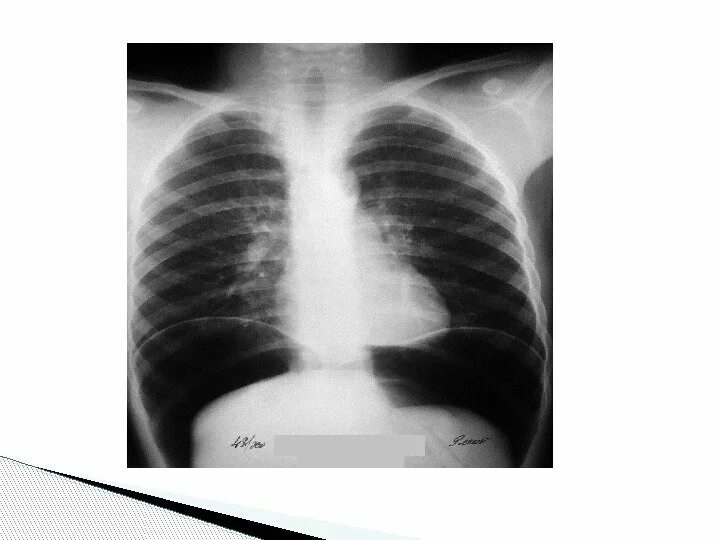

Коллапсотерапия при туберкулезе